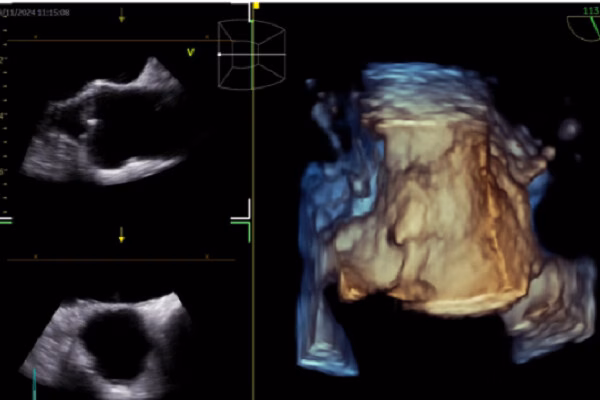

TS-BS Giang Minh Nhật chia sẻ về ứng dụng Trí tuệ nhân tạo (AI) trong tái định hình chăm sóc tim mạch tại hội nghị khoa học thường niên Bệnh viện Nhân dân Gia Định. AI được ứng dụng rộng rãi trong hình ảnh học tim mạch, ECG, siêu âm tim, CT, MRI tim và quyết định lâm sàng.